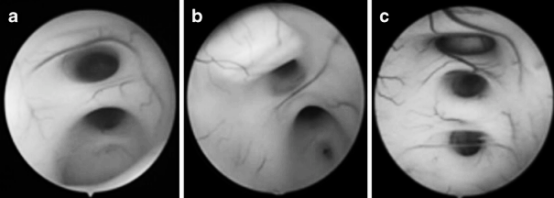

图4 内镜下第三脑室的不同表现,提示脑室解剖结构日益扭曲。a. 被下丘脑粘连分为两部分;b. 被下丘脑粘连分为两部分,视野下方可见导水管;c. 被两处下丘脑粘连分为三部分。